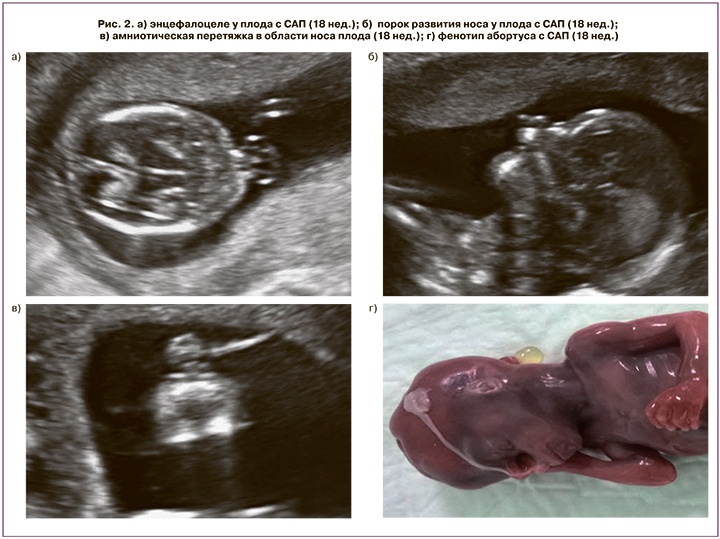

Беременная Л., 26 лет, беременность 2-я, предстоящие роды – 1-е, обратилась в Перинатальный медицинский центр после проведения амниоцентеза и исключения хромосомных аномалий по месту жительства в связи с наличием пороков развития и маркеров хромосомной патологии в виде энцефалоцеле, аплазии носовых костей, аномальной установки пальцев кисти. При ультразвуковом исследовании в сроке 18 недель выявлены затылочное энцефалоцеле (рис. 2, а), грубая лицевая расщелина, отсутствие структур носа (рис. 2, б), патология кисти, имитирующая синдактилию и олигодактилию. Детальная оценка головы, лица и конечностей позволила визуализировать амниотические тяжи в виде нитевидных структур, примыкающих к измененным сегментам плода, не имеющим связи с плодными оболочками и стенкой матки (рис. 2, в). Данная эхографическая картина позволила интерпретировать данный комплекс пороков развития, как САП. Семья приняла решение о прерывании беременности (рис. 2, г).